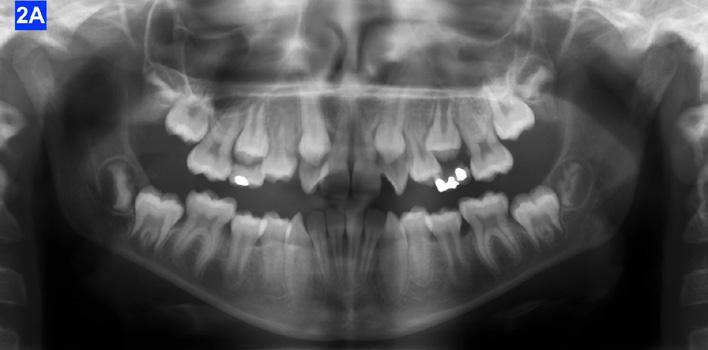

Panoramic radiogram revealed a late mixed dentition with un-erupted wisdom teeth and second molars. A significant finding was noted in that the maxillary cuspids were in transposition with the lateral incisors. There was excellent bone support and no sign of periodontal or peri-apical pathology (Figure 2-A).

Figure 2A: Pre-treatment, Panoramic radiogram Figure 2B: Pre-treatment, lateral Cephalometric radiogram